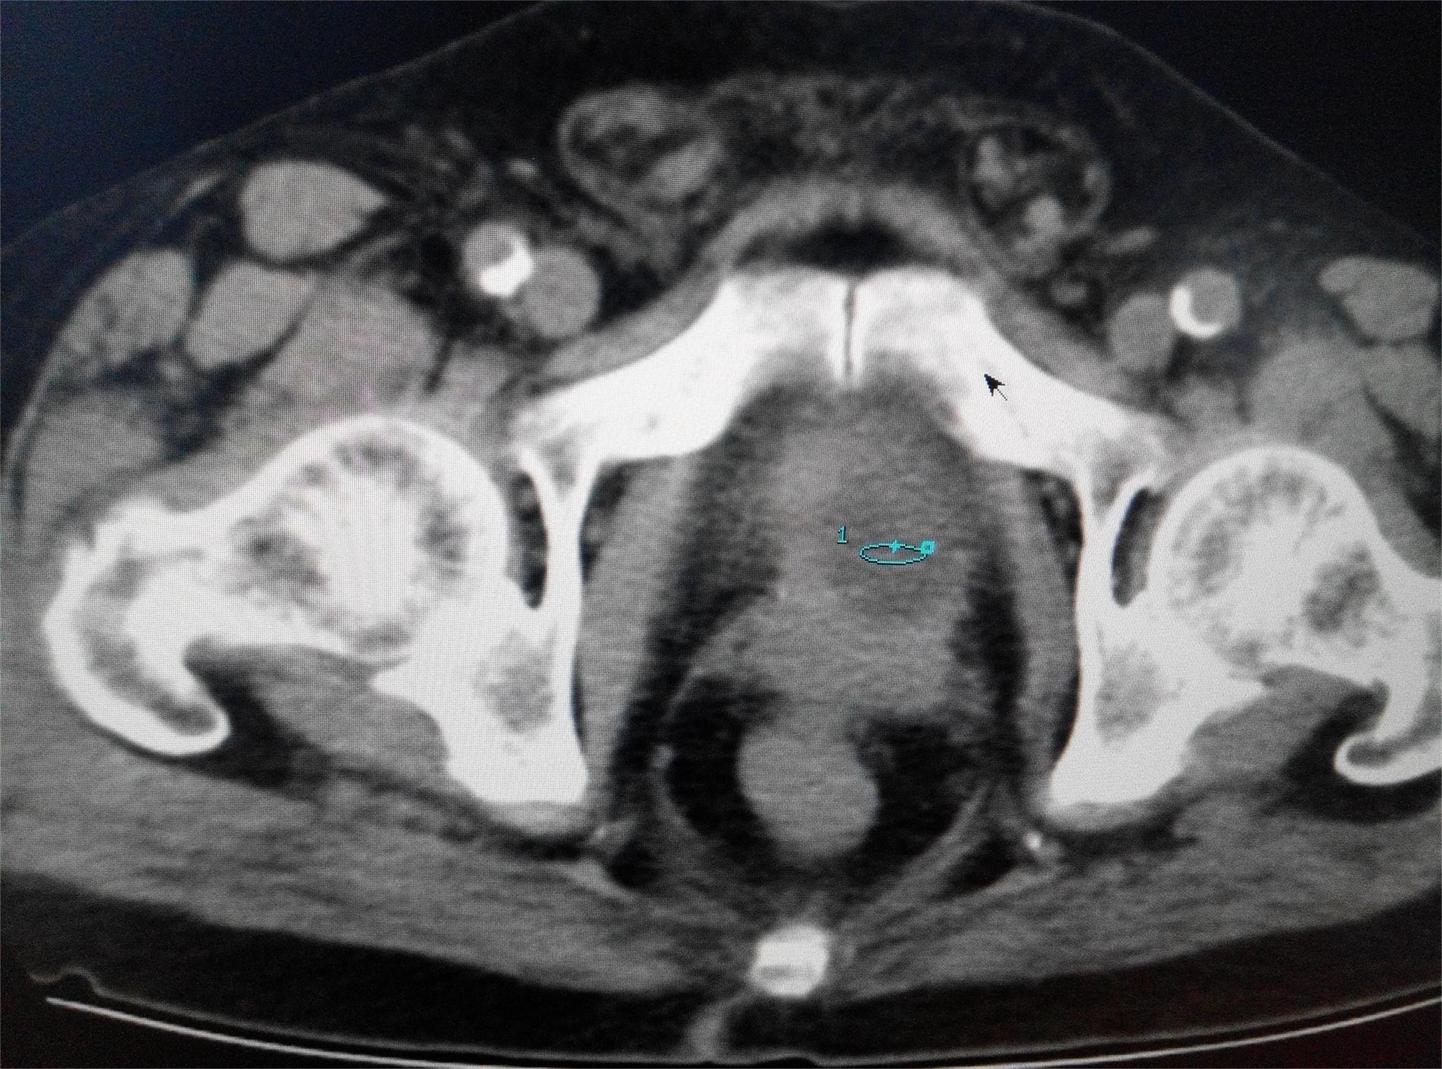

CT51546:请会诊,病人,男,88岁。

本帖最后由 cefcmj 于 2016-1-19 20:59 编辑 病人前列腺癌术后,出现血尿,麻烦各位老师看看膀胱和肾脏。

1)前列腺术后改变。

2)双侧肾脏萎缩并双肾多发囊肿。

3)膀胱下壁略厚(考虑累及可能)、进一步MRI检查。

左肾多发性囊性占位,膀胱左后壁稍增厚,左侧精囊腺变小,考虑:前列腺癌术后,膀胱精囊腺受浸?左肾囊肿可能性大。

左肾占位性病变,建议增强进一步检查

前列腺癌复发伴左肾转移,建议增强